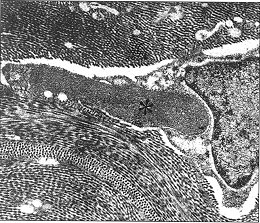

图7 A稠密的原纤维粒物质的沉积物(星号)与角膜细胞毗连(×30000)